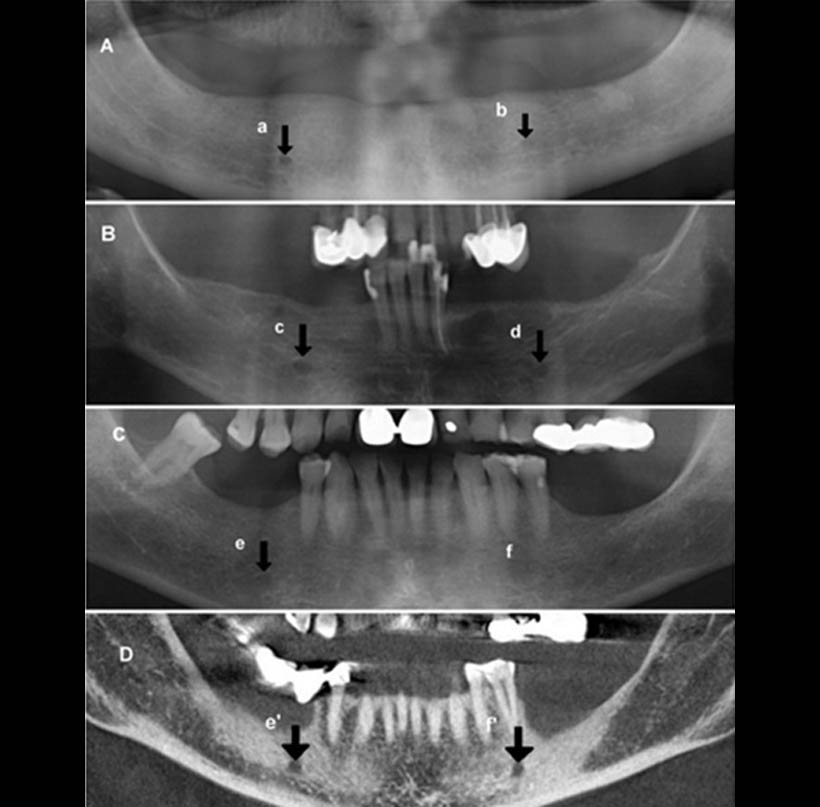

Fig. 1. Foramen mental en las radiografías panorámicas (A, B, C): continua (a), (c, d) separados, (b, e) difusas, y no identificados (f) (yosue y Brooks). Foramen mental en la TC de haz cónico (D): el agujero mentoniano izquierdo (f ‘) se visualizaron utilizando la reconstrucción para-panorámica correspondiente al paciente C.